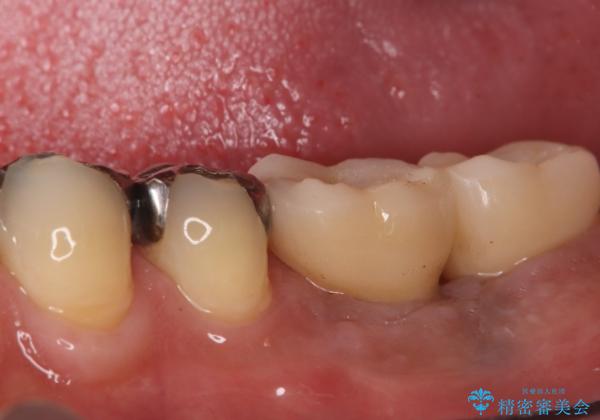

- 治療計画

今回の治療では、まず左下6番と7番の欠損部に、骨の状態を考慮しながら慎重に2本のインプラントを埋入しました。インプラント体と骨がしっかりと結合するのを待った後、最短の期間で最終的な被せ物を装着するための精密な型取りを実施。最終的に、周囲の歯と調和した審美性の高いセラミック製の歯を装着しました。